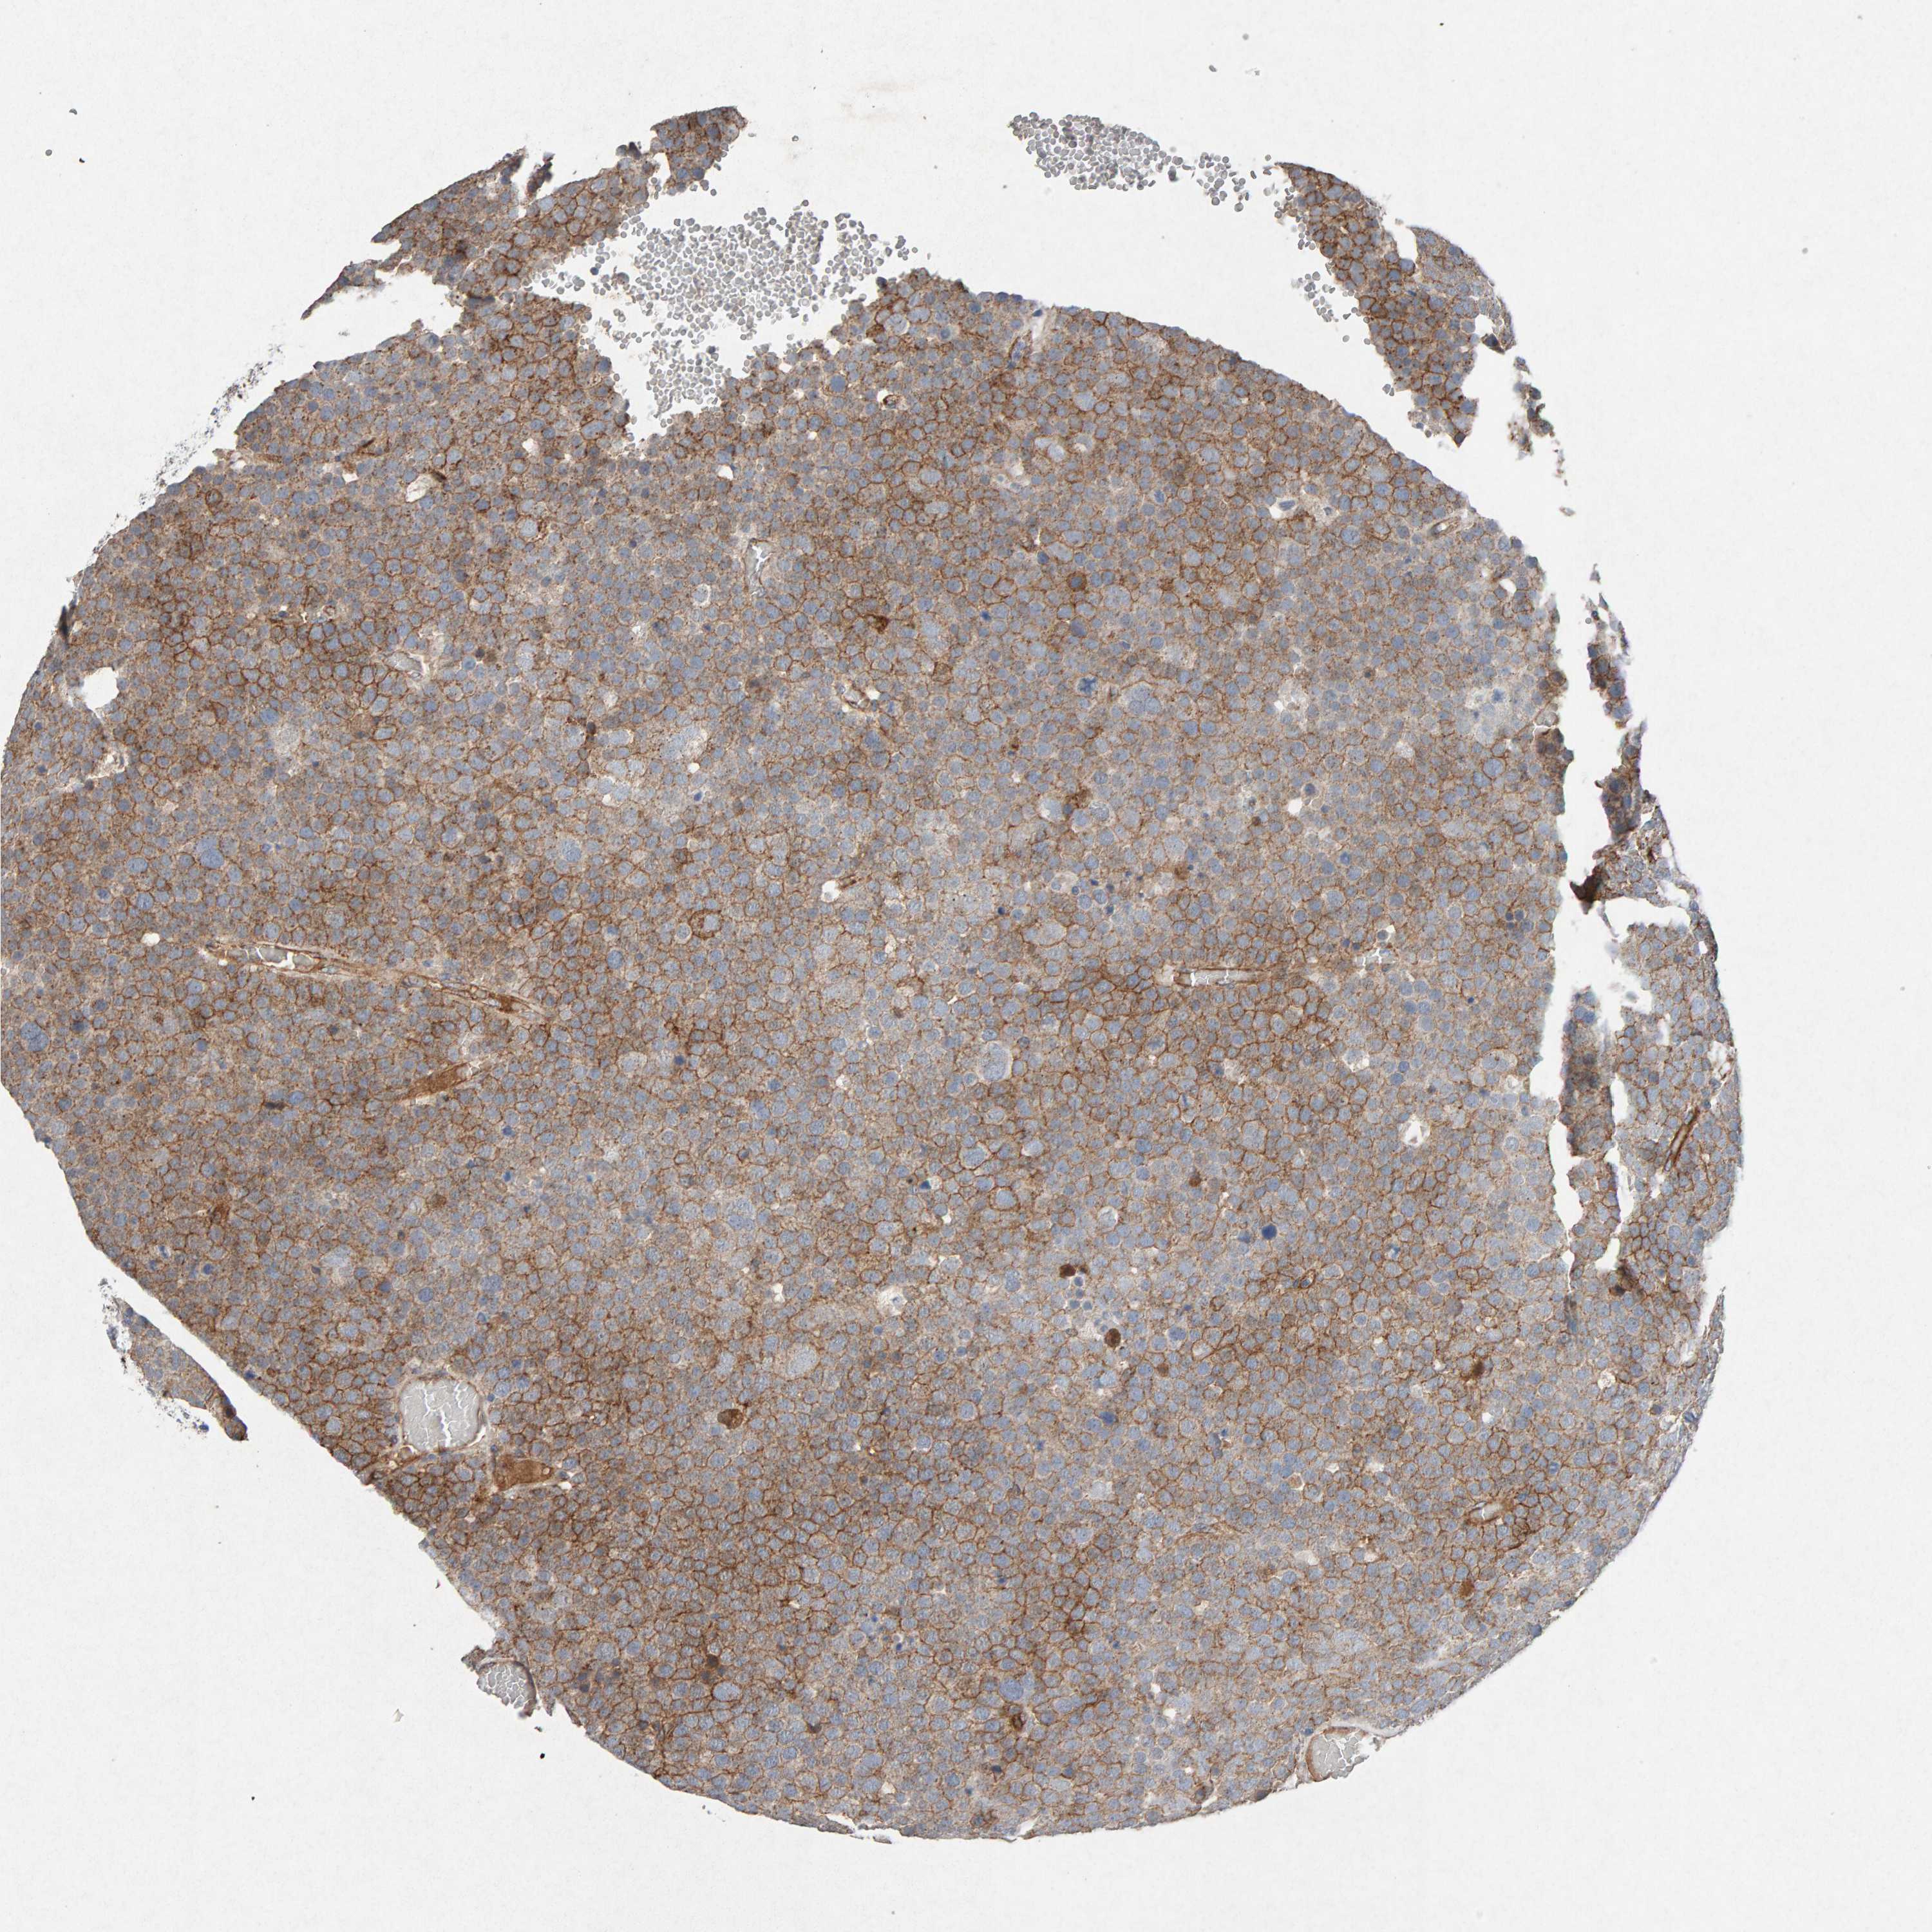

TESTIS CANCER - Protein expressioni

A mouse-over function shows sample information and annotation data. Click on an image to view it in a full screen mode. Samples can be filtered based on level of antibody staining by selecting one or several of the following categories: high, medium, low and not detected. The assay and annotation is described here.

Note that samples used for immunohistochemistry by the Human Protein Atlas do not correspond to samples in the TCGA dataset.

Antibody stainingi

Antibody staining in the annotated cell types in the current human tissue is reported as not detected, low, medium, or high, based on conventional immunohistochemistry profiling in selected tissues. This score is based on the combination of the staining intensity and fraction of stained cells.

Each image is clickable and will lead to virtual microscopy that enables deeper exploration of all samples and also displays staining intensity scores, fraction scores and subcellular localization as well as patient and tissue information for each sample.

Antibody CAB022442

Antibody CAB022443

Staining

High

Medium

Low

Not detected

Intensity

Strong

Moderate

Weak

Negative

Quantity

>75%

75%-25%

<25%

None

Location

Nuclear

Cytoplasmic/membranous

Cytoplasmic/membranous,nuclear

Carcinoma, Embryonal, NOS

Seminoma, NOS